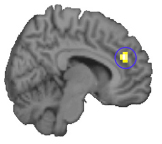

Die Region im Präfrontalkortex, die bei der Schärfung der Wahrnehmung („Wahrnehmungs-lernen“) eine Rolle spielt. mod. nach Kahnt et al., 2011